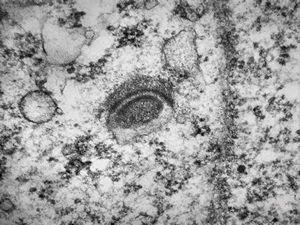

M,21y. | annulate lamellae - intracranial germinoma

M,21y. | annulate lamellae - intracranial germinoma